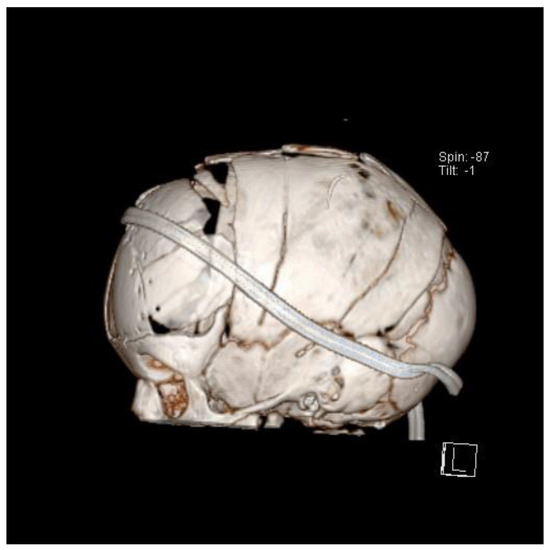

8. Surgical Techniques

- Jugović, D.; Spazzapan, P. Endoskopsko zdravljenje skafocefalije: Prikaz primera in nove operacijske tehnike. Zdr. Vestn. 2015, 84, 642–648. [Google Scholar] [CrossRef]